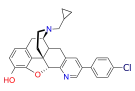

- 4-Chlorophenylpyridomorphinan

4-chlorophenylpyridomorphinan 4-chlorophenylpyridomorphinan |